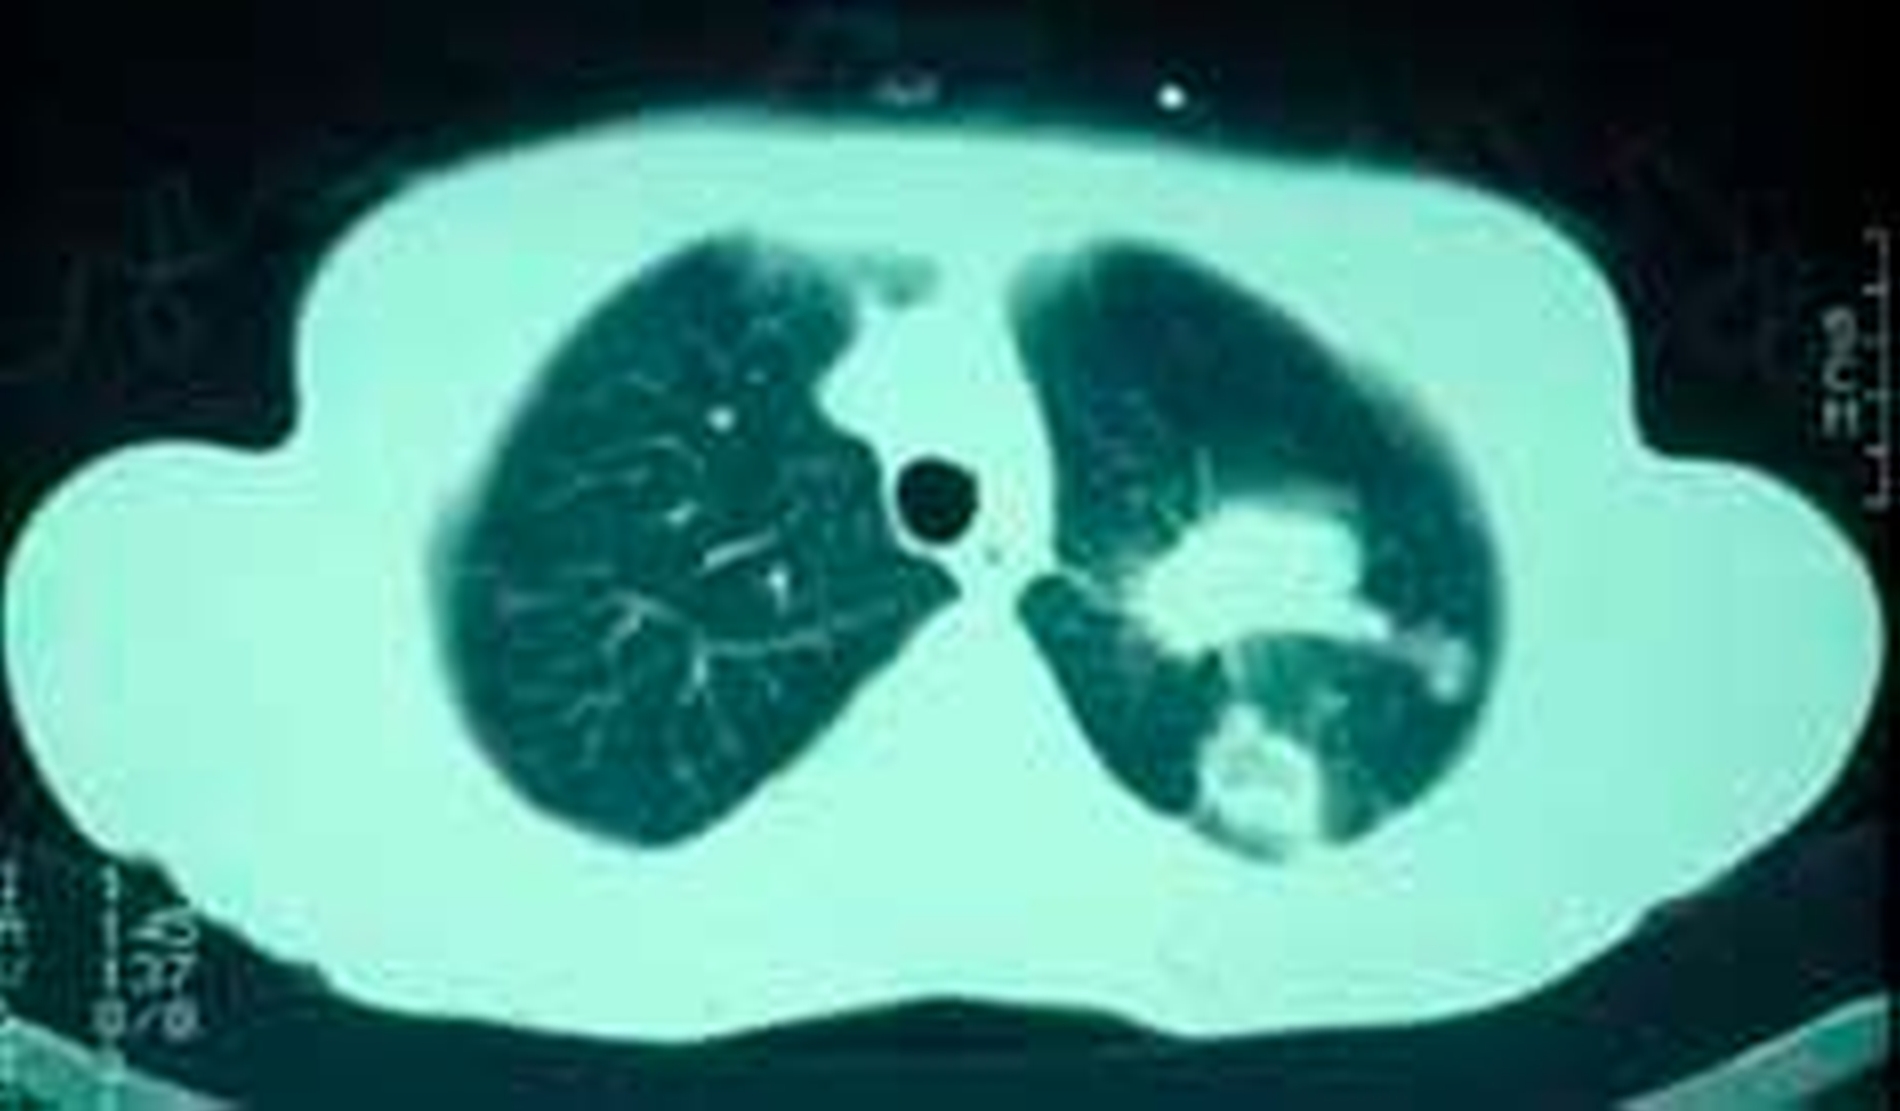

Die histologische Untersuchung der Gewebeprobe zeigte maligne, anaplastische, zytoplasmaarme Zellen mit ausgeprägter Kernpolymorphie und Hyperchromatismus (Abb. 5). Das im Rahmen der anschließenden Primärtumorsuche durchgeführte Computertomogramm des Thorax führte schließlich zur Entdeckung eines zentralen, kleinzelligen Bronchialkarzinoms im Bereich der linken Lunge (Abb. 6). Wenige Monate später verstarb die Patientin an ihrem Tumorleiden.